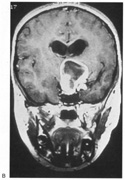

Achromatopsia in the contralateral hemifield alone can follow unilateral right or left occipital lesions (Fig. 18). Patients are typically asymptomatic until the defect is demonstrated on examination.234,235 Hemiachromatopsia is usually associated with a superior quadrantanopia;234,235,241 therefore, the color defect is only demonstrable in the remaining inferior quadrant. The preserved color vision in the ipsilateral hemifield allows normal or near-normal performance on centrally viewed tests of color vision such as pseudoisochromatic plates. The incidence of hemiachromatopsia is probably underestimated, given its asymptomatic nature and the failure of routine clinical color tests to detect its presence.

Fig. 18. Magnetic resonance imaging scan of patient with stroke causing a right hemiachromatopsia as well as partial superior quadrantanopia.